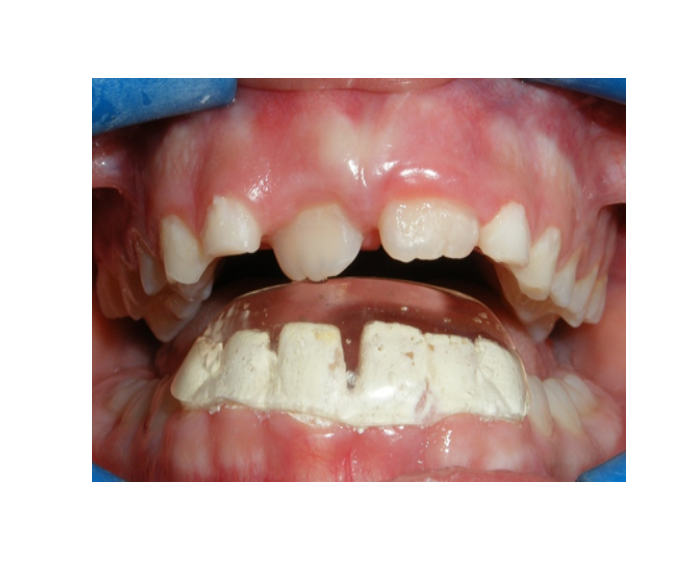

Mordida cruzada posterior bilateral